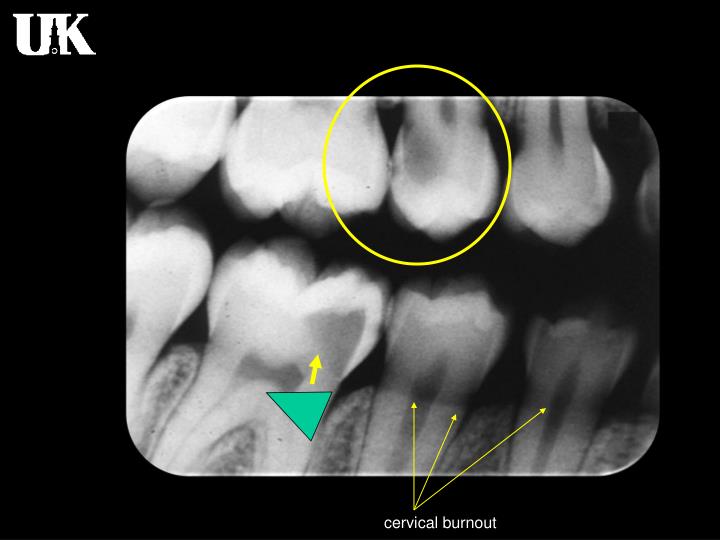

Dental X Ray Burnout . Radiologists are no exception, with up to 46% of. Accurate interpretation of dental caries starts with accurate radiograph. The presence or absence of cervical burnout on interproximal surfaces of maxillary first and second molars was evaluated by two oral & maxillofacial radiologists. Cervical burnout versus dental caries. Two phenomena (cervical burnout and mach band) create radiolucent areas that can mimic carious lesions. Burnout is an extremely prevalent issue among healthcare professionals. Cervical burnout appears as a radiolucent band around the necks of teeth and is more pronounced at the proximal edges.